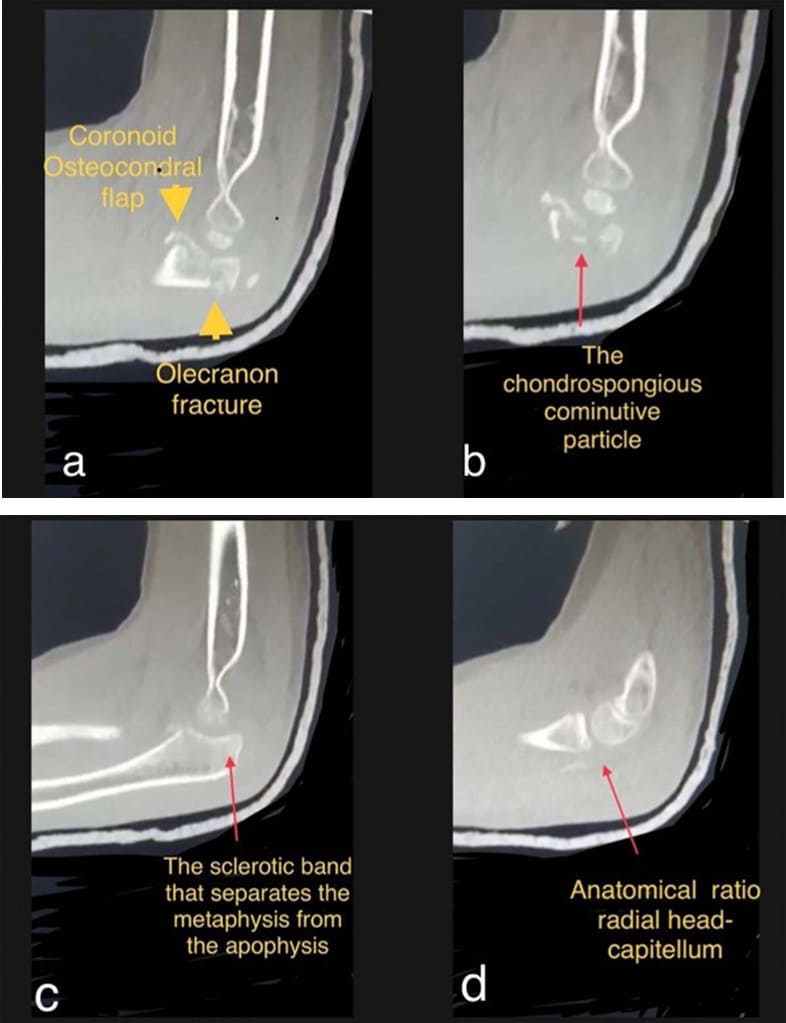

Figure 3: CT images confirm the olecranon fracture and identify a coronoid fracture. a) The characteristic appearance of the paediatric coronoid fracture; the chondral flap involves the entire distal trochlear compartment. b) The comminute particle at the junction of the two fractures. c) The sclerotic area of least resistance; the olecranon fracture crosses this area. d) Radial head dislocation was reduced.